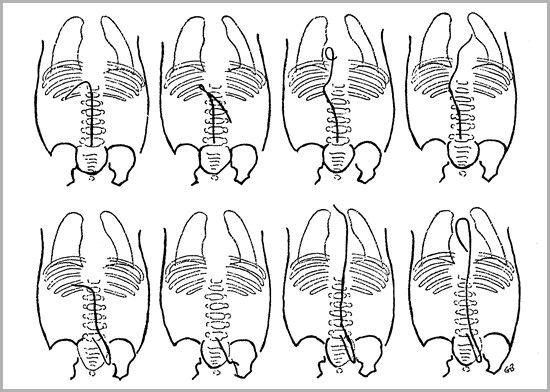

UAC and UVC Positions

Both should be above the diaphragm

UAC should be between T6 and T9

UVC should be in the IVC as it enters theright atrium (T8-T9)

Double lumen catheter is usually, but notalways, UVC

Umbilical Venous Catheters

Umbilical Arterial Catheters

Tip inintrahepaticportal branch

Umbilical Venous Catheters

Umbilical Arterial Catheters

Portal vein intosup. Mesentericvein

Umbilical Venous Catheters

Umbilical Arterial Catheters

Right atrium

Umbilical Venous Catheters

Umbilical Arterial Catheters

Passes thruinteratrialcommunicationinto left atrium-need lateral

Umbilical Venous Catheters

Umbilical Arterial Catheters

Midabdominallocation is in eitherceliac, renal orsuperior mesentericartery

Umbilical Venous Catheters

Umbilical Arterial Catheters

External iliacartery

Umbilical Venous Catheters

Umbilical Arterial Catheters

Brachiocephalicor carotidarteries

Umbilical Venous Catheters

Umbilical Arterial Catheters

Ascending aorta-could enter leftventricle